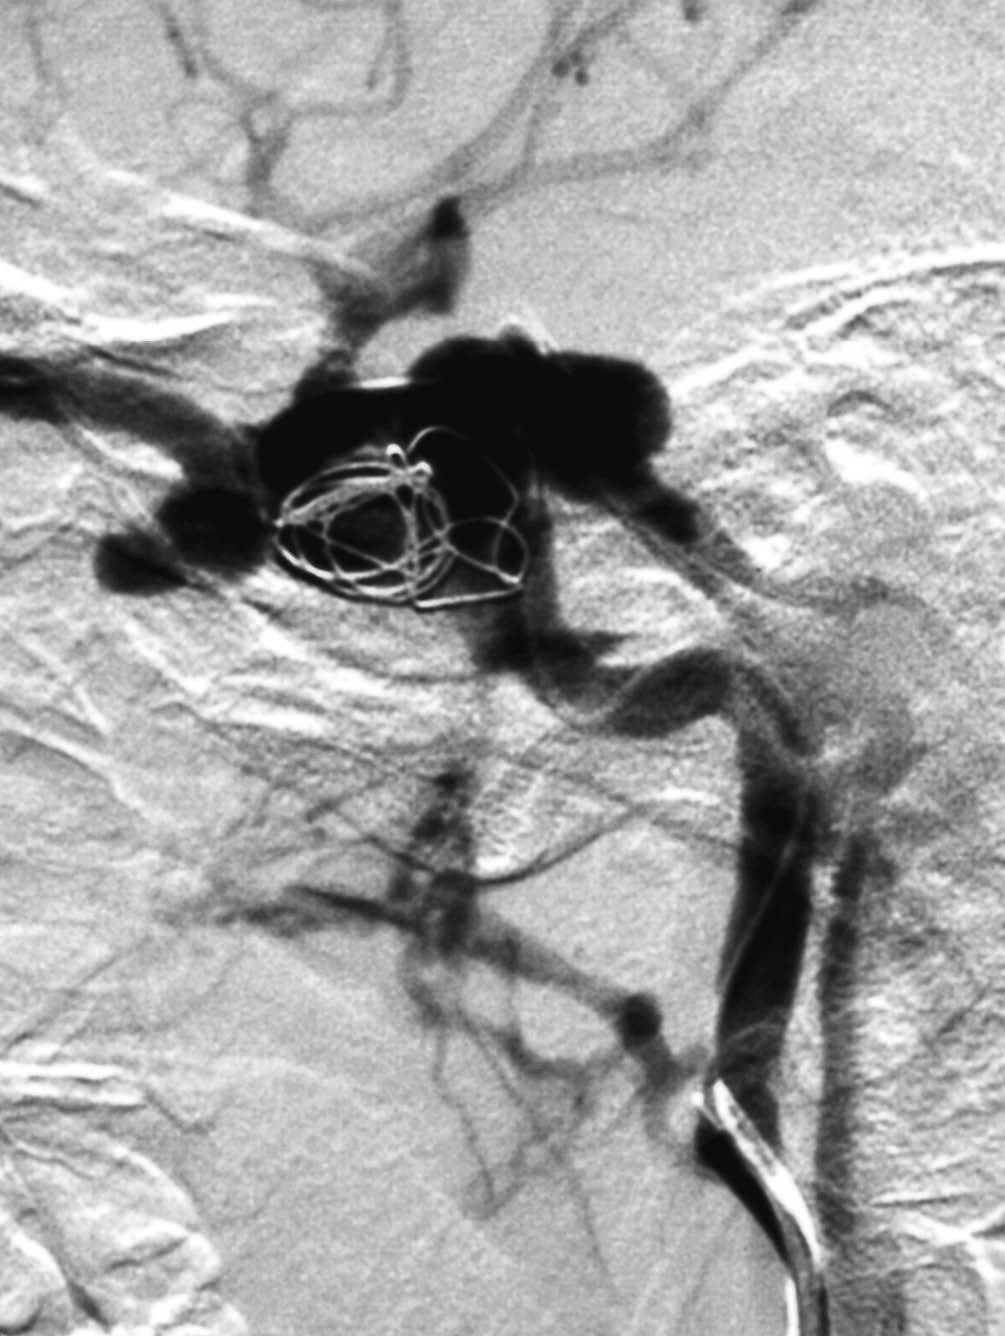

En los casos en los que el tratamiento conservador no ha sido eficaz10, cuando existen manifestaciones clínicas o angiográficas que asocian mal pronóstico, que ya hemos comentado, está indicada la terapia endovascular. La vía de abordaje puede ser arterial o venosa. Inicialmente se prefería la colocación de balones por vía arterial27-29. Con este procedimiento se conseguía cierre de la fístula con preservación de ACI casi en el 90% de los casos, sin embargo la tasa de complicaciones mayores era del 5%, consistiendo en isquemia cerebral transitoria e infartos tromboembólicos o isquémicos30. Los pseudoaneurismas post-tratamiento aparecían hasta en un 44% de los casos y se debían al hueco dejado por el desinflado del balón, pero su trascendencia clínica era escasa28,31. Hoy en día este procedimiento ha sido sustituido por otros gracias al desarrollo y empleo de nuevos materiales y/o vías de abordaje32. Se prefieren los coils en la práctica habitual (fig. 4).

Fig. 4.--A) Arteriografía cerebral con inyección de contraste desde la arteria carótida interna (ACI) en proyección lateral demuestra la existencia de una brecha o fístula directa, de alto flujo, en la porción intracavernosa en una paciente de 28 años con antecedente traumático. Asimismo se observa flujo venoso retrógrado a la vena oftálmica, que está muy dilatada. B) Cateterización selectiva de ACI y colocación de coils en el seno cavernoso por vía transarterial. C) Control arteriográfico tras la embolización transarterial con coils, con inyección de contraste en ACI, en fase arterial y proyección lateral, donde se aprecia empaquetamiento del seno cavernoso. Persiste todavía la dilatación de la vena oftálmica, que desapareció a los pocos días, con mejoría clínica completa.

En nuestro grupo de 10 pacientes con FCC directa tratada mediante embolización, en 5 procedimientos el abordaje fue por vía arterial exclusivamente, colocando como material embolígeno en 2 casos balones y en 3 coils (fig. 4). En 4 casos la mejoría de la sintomatología fue completa, mientras que en uno fue parcial. Tan sólo en un paciente se tuvo que realizar la exclusión completa de la arteria carótida ya que la ACI estaba muy deteriorada. Previamente realizamos el test de oclusión con objeto de conocer cuál sería el efecto de la exclusión carotídea.